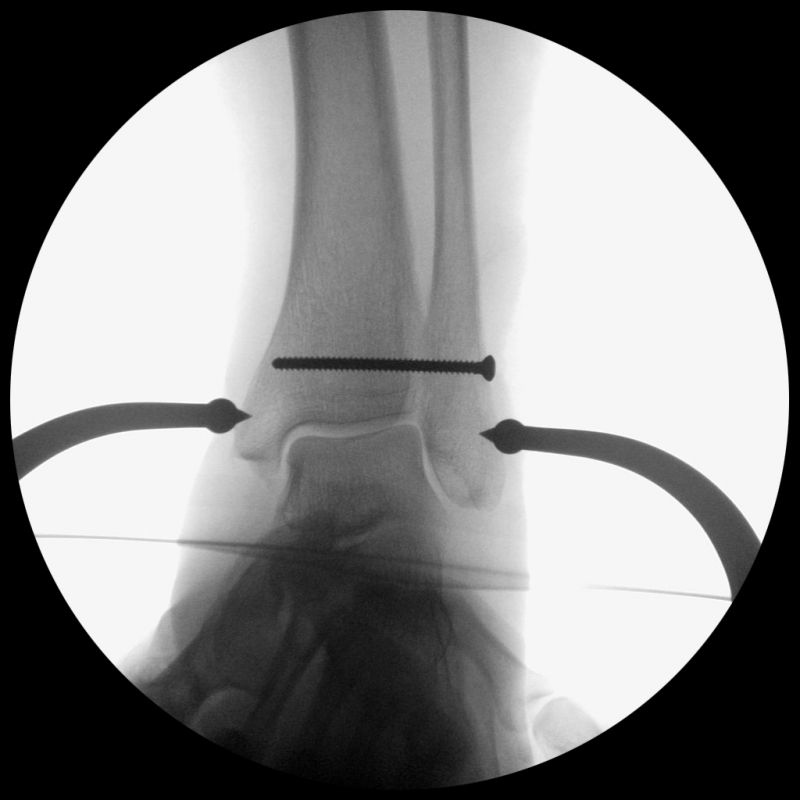

Die eigentliche Reposition der Syndesmose erfolgt mittels einer Repositionszange über dem Malleolus medialis und lateralis, entlang der Achse des oberen Sprunggelenkes und wird nach Reposition in anatomischer Stellung fixiert 52. Dabei ist auf eine Neutralstellung im oberen Sprunggelenk zu achten. Die temporäre Fixierung des DTFG kann mittels Schraube(n) oder einem dynamischen System (Suture Button - z.B. Tight-Rope, Fa. Arthrex™) erfolgen. Bei der Fixierung mittels Schraube können eine oder zwei Schrauben von 3,5-4,5 mm Stärke, tri- oder quadricortical, verwendet werden 53. Dies werden am posterolateralen Rand der Fibula in leicht aufsteigender Technik (30°), circa 2 cm und 3,5 cm oberhalb der tibiotalaren Gelenkfläche, parallel zur OSG-Achse nach entsprechendem Vorbohren eingebracht. Eine Schraubenpositionierung 2 cm oberhalb der tibiotalaren Gelenkfläche konnte in biomechanischen Untersuchungen eine bessere biomechanische Stabilität des DTFG gewährleisten als eine Positionierung der Schraube weiter proximal 54. Keinen Vorteil gegenüber tricortical eingebrachten Stellschrauben wiesen dagegen Schrauben auf, welche vier Corticalices fassen 55. Ob eine Entfernung der Syndesmosenstellschraube sinnvoll ist oder nicht, ist bist heute Bestandteil der internationalen Diskussion 56. Wir Entfernen Stellschrauben nach ca. 6 Wochen bei erhaltenem PITFL, sind alle Syndesmosenbänder verletzt, wird die Stellschraube 8 Wochen belassen.